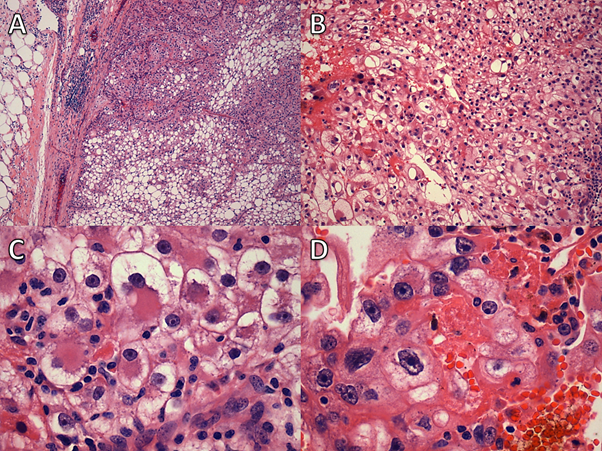

Figure 3

Figure 3. Case 1: A and B. Clear-cell renal cell carcinoma, grade 3; high- and low-power fields of the two papillary adenomas are shown in C and D and E and F.